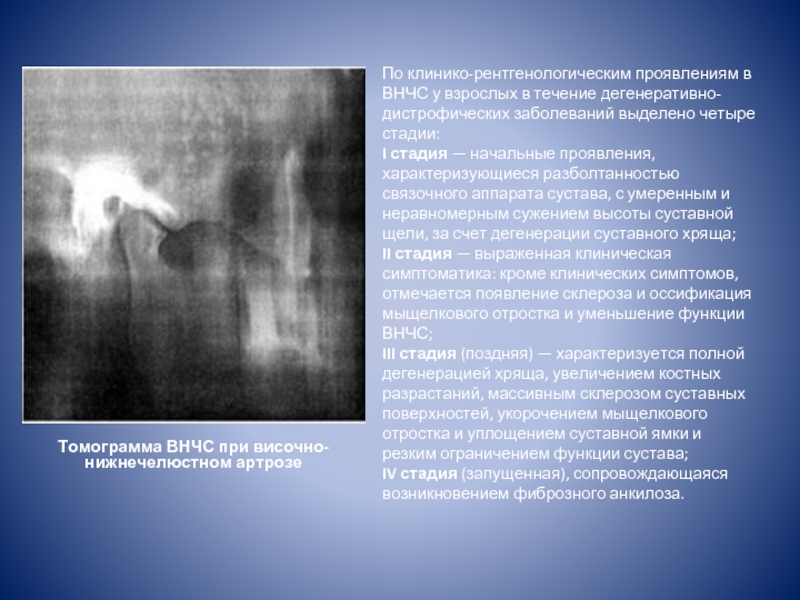

Дистрофические заболевания внчс презентация - 89 фото